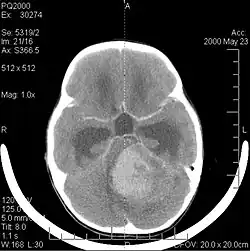

Durch Computertomographie (CT) und Kernspinresonanztomographie (MRT) kann eine Neoplasie im Gehirn effektiv nachgewiesen werden. Zur Identifizierung von Läsionen ist die MRT empfindlicher als die CT, weist aber für Patienten mit Herzschrittmachern, inkompatiblen Prothesen, Metallklammern und anderem Kontraindikationen auf. Die CT bleibt die Methode der Wahl, um Verkalkungen innerhalb der Läsionen oder Knochenerosionen der Schädeldecke oder -basis zu erkennen. Die Verwendung von Kontrastmitteln, die im Fall der CT jodiert und im Fall der MRT paramagnetisch (Gadolinium) sind, ermöglicht die Erfassung von Informationen über die Vaskularisation und Integrität der Blut-Hirn-Schranke, eine bessere Definition der Tumorgeschwulst im Vergleich zum umgebenden Ödem und die Erstellung von Hypothesen über den Grad der Malignität. Die radiologische Untersuchung ermöglicht auch eine Bewertung der mechanischen Auswirkungen und die daraus resultierenden Veränderungen der Gehirnstrukturen, die sich durch den Tumor ergeben, wie zum Beispiel Hydrocephalus und Hernien, deren Auswirkungen tödlich sein können. Schließlich kann mit dieser Diagnostik in Vorbereitung einer Operation der Ort der Läsion oder die Infiltration des Tumors in lebenswichtige Bereiche des Gehirns bestimmt werden. Zu diesem Zweck ist die MRT effizienter als die CT, da sie dreidimensionale Bilder liefern kann.[4]

Diagnostische radiologische Bildgebungsinstrumente heben die Veränderung des neoplastischen Gewebes im Vergleich zum normalen Gehirnparenchym hervor (durch Änderungen der elektronisch dargestellten Dichte des Gewebes bei der CT und der Signalintensität bei der MRT). Wie die meisten pathologischen Gewebe sind auch Tumoren durch eine erhöhte Ansammlung intrazellulären Wassers erkennbar. Im Computertomogramm erscheinen sie hypodens, das heißt von geringerer Dichte als das Gehirnparenchym, im Kernspinresonanztomogramm bei Spin-Gitter-Relaxation hypointens und bei Spin-Spin-Relaxation sowie Protonengewichtung (PD) hyperintens.[5][6]

Die Computertomographie des Gehirns zeigt typischerweise eine Gewebsmasse, die entweder durch Kontrast verstärkt werden kann. Bei der CT erscheinen niedriggradige Gliome normalerweise isodens zum normalen Parenchym und zeigen daher möglicherweise keine Kontrastverstärkung. In ähnlicher Weise sind Läsionen in der Fossa cranii posterior, der hinteren Schädelgrube, im CT schwer zu identifizieren. Folglich sind die Ergebnisse einer solchen Tomographie allein nicht immer für diagnostische Zwecke ausreichend.[4] In zweifelhaften Fällen ist die Verwendung der empfindlicheren Kernspintomographie unerlässlich.